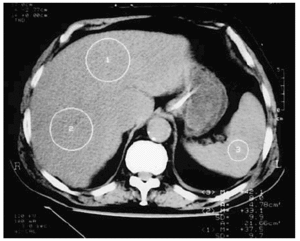

Desde la consola, con el cursor se marcaban 5-8 zonas en el hígado y otras 3-5 de igual superficie en el bazo, y el radiólogo de guardia leía la diferencia de densidades entre ambos en unidades Hounsfield (UH) (fig. 1). El número de zonas seleccionadas fue considerado como adecuado para esta valoración por el radiólogo encargado del estudio.

Figura 1. Imagen de la TC con valores normales de las densidades, medidas en unidades Hounsfield, del hígado y del bazo.

La TC fue reevaluada por otro médico especialista en radiodiagnóstico unas horas más tarde (ambos desconocían los diagnósticos clínicos del donante), y dado que las densidades del hígado y el bazo son similares (40-50 UH), se consideró como una TC normal cuando la diferencia de densidades entre el hígado y el bazo era menor de 4-6 UH. Se definió en la TC como una EH moderada cuando la diferencia de densidades entre el bazo y el hígado cuya densidad disminuye debido a la presencia de grasa era mayor de 10 UH y menor de 19 UH, y como EH grave cuando la diferencia era ≥ a 20 UH (fig. 2).